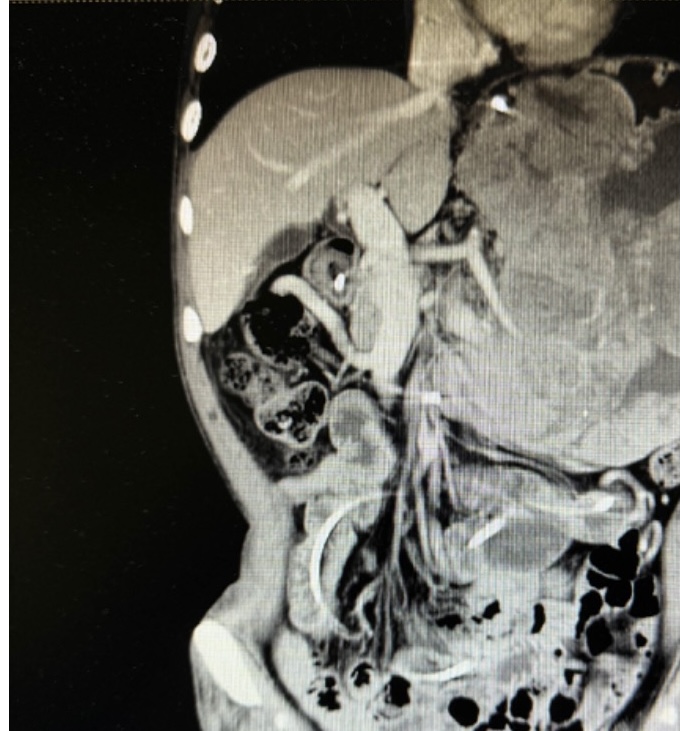

张翼主任医师接诊后,第一时间牵头对患者进行全面评估,经影像检查进一步确认:肿瘤体积巨大且与脾动脉粘连紧密,术中稍有不慎就可能引发致命性大出血,手术难度远超常规胃肠肿瘤手术。为最大程度降低风险,张翼教授先后多次组织全院大会诊,联合麻醉科、输血科、重症医学科、影像医学科等多学科专家反复推演手术方案,从手术入路的选择、血管保护的细节,到术中输血预案、术后并发症防控,每一个环节都制定了详尽的应对策略。

患者术前影像资料